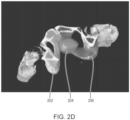

• the systems and methods described herein identify, along with the prostate, various additional tissue volumes within the CT image.

• additional tissue volumes corresponding to pelvic bones, a bladder, a rectum, and gluteal muscles of the subject may be identified in addition to the prostate.

• the identification of such additional tissue volumes can be used for a variety of functions and confers advantages over other approaches, such as a binary classification approach wherein voxels of the CT image are either identified as corresponding to prostate or not.

• identification of additional tissue volumes can, for example, (i) improve the accuracy with which the CNN module identifies the prostate volume within the CT image, (ii) provide for identification of reference regions that can be used to compute normalization values for uptake metric calculation, and (iii) allow for intensities of SPECT image voxels corresponding to prostate to be corrected for cross-talk that results, for example, from the accumulation of radiopharmaceutical within the bladder.

• the second machine learning module 1208 may also identify additional tissue volumes corresponding to additional tissue regions within the subject, such as a left gluteal muscle, a bladder, and left and right hip bones.

• a tissue volume corresponding to a left gluteal muscle of the subject may be used as a reference volume, for example to compute a background value in determining a TBR value for the subject, as described herein.

• a tissue volume corresponding to a bladder of the subject may be used for correcting intensity values of voxels of a SPECT image for bladder cross-talk, for example as described herein, in section B "Correcting for Bladder Intensity Bleed Through".

• Identified tissue volumes corresponding to a left and right hip bone of the subject may be used for post-processing.

• a second machine learning module also referred to as a base Single Segmentation Machine 1208 (SingleSegMachine (base) in FIG. 12 ) performs a high-resolution segmentation of a CT image to identify a prostate volume corresponding to a prostate of the subject, along with additional tissue volumes corresponding to specific tissue regions, such as left and right gluteal muscles, a rectum, a bladder, a sacrum and coccyx, and left and right hip bones.